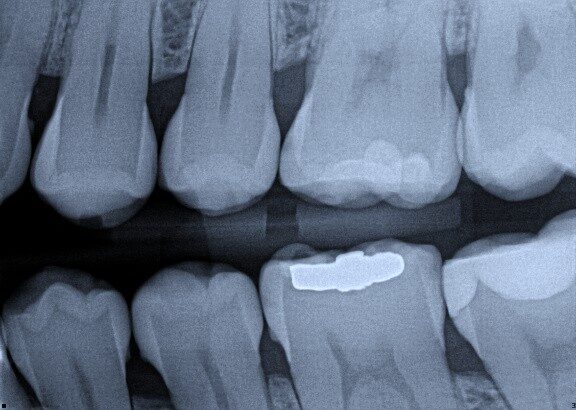

The radiograph shows evidence of

The radiograph shows evidence of calculus on

There is radiographic evidence of

Regarding tooth 4.6, there is evidence of

Which of the following is/are seen in the radiograph?

Which of the following is/are seen in the radiograph for tooth 3.6?

Which of the following is/are seen in the radiograph for tooth 3.7?

The radiograph shows evidence of periodontal bone loss on